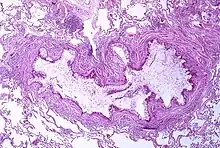

A tissue cross section of the airway showing a stained pink wall and an inside full of white mucous

Obstruction of the lumen of a bronchiole by mucoid exudate, goblet cell metaplasia, and epithelial basement membrane thickening in a person with asthma

Asthma is the result of chronic inflammation of the conducting zone of the airways (most especially the bronchi and bronchioles), which subsequently results in increased contractability of the surrounding smooth muscles. This among other factors leads to bouts of narrowing of the airway and the classic symptoms of wheezing. The narrowing is typically reversible with or without treatment. Occasionally the airways themselves change.[22] Typical changes in the airways include an increase in eosinophils and thickening of the lamina reticularis. Chronically the airways' smooth muscle may increase in size along with an increase in the numbers of mucous glands. Other cell types involved include T lymphocytes, macrophages, and neutrophils. There may also be involvement of other components of the immune system, including cytokines, chemokines, histamine, and leukotrienes among others.[21]